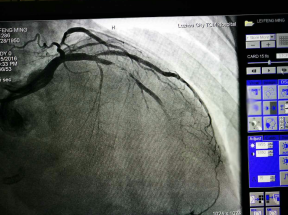

為求明確診斷及進(jìn)一步治療,周阿姨慕名來到了我院心血管內(nèi)科住院診治。經(jīng)冠狀動脈造影檢查,發(fā)現(xiàn)原來植入的支架發(fā)生了99%的狹窄,即支架內(nèi)再狹窄,這就是導(dǎo)致她目前再次出現(xiàn)活動后胸悶胸痛的根本原因。

術(shù)前